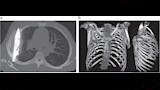

في واقعة طبية نادرة، اكتشف أطباء في تنزانيا شفرة سكين معدنية كبيرة مستقرة داخل تجويف صدر رجل يبلغ من العمر 44 عاما، بعد مرور ثماني سنوات على تعرضه لطعنات متكررة دون أن يعلم ببقاء الشفرة في جسده.

وأظهرت الفحوص السريرية أن الجزء الأيمن من صدره لا يتمدد بالكامل أثناء التنفس، فيما كشفت الأشعة السينية وجود شفرة سكين كبيرة عالقة في تجويف الصدر، ممتدة من الظهر إلى مقدمة القفص الصدري، ومحاطة بطبقات من القيح والأنسجة الميتة.